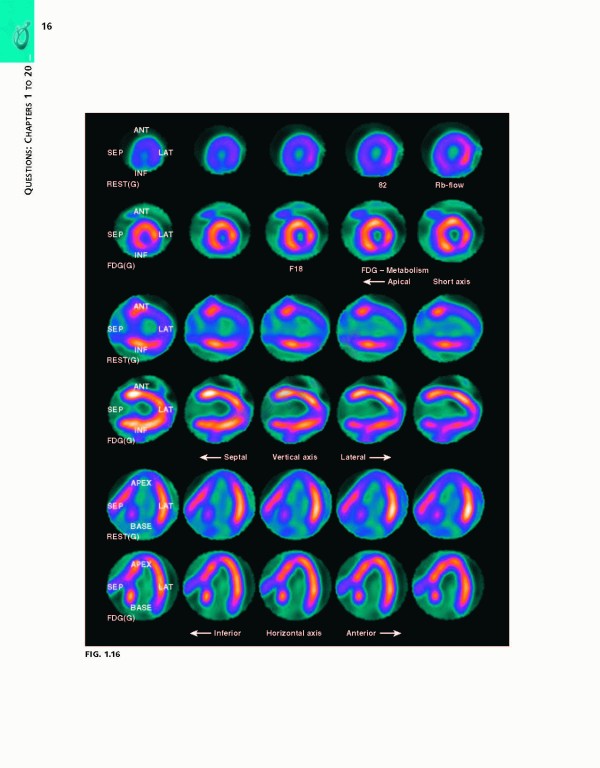

کتاب Braunwalds Heart Disease Review and Assessment 2019، بررسی و ارزیابی بیماری قلبی براونوالد ویراست یازدهم شامل تصاویر و تصاویر کاملاً رنگی که مطالعه شما را بهبود بخشیده و حفظ مواد پیچیده را بهبود می‌بخشد.

With more than 700 review questions derived from and keyed to the newly revised 11th Edition of Braunwald's Heart DiseaseBraunwald’s Heart Disease Review and Assessment, 11th Edition, is the perfect review tool for fellows, residents, and practitioners to prepare for board exams in cardiovascular medicine. Noted Harvard educator Dr. Leonard S. Lilly, with assistance from faculty and fellows at Brigham & Women’s Hospital, provides a thorough, clear, and concise overview of the entire field, helping ensure your mastery of all key aspects of today’s cardiology. This title is a one-stop resource for complete, authoritative coverage of the most important concepts in cardiovascular medicine – ideal for self-assessment, individualized study, and clinical practice.

• Contains full-color images and illustrations throughout, and numerous case studies that enhance your study and improve retention of complex material.